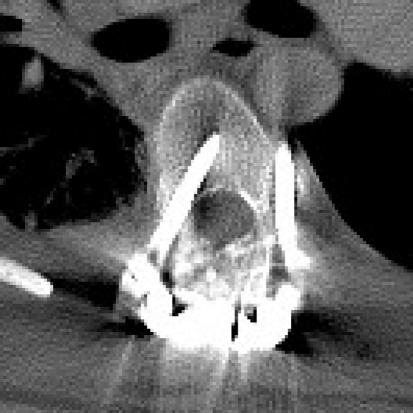

Free-hand thoracic pedicle screw placement is becoming more prevalent within neurosurgery residency training programs. This technique implements anatomic landmarks and tactile palpation without fluoroscopy or navigation to place thoracic pedicle screws. Because this technique is performed by surgeons in training, we wished to analyze the rate at which these screws were properly placed by residents by retrospectively reviewing the accuracy of resident-placed free-hand thoracic pedicle screws using computed tomography imaging. A total of 268 resident-placed thoracic pedicle screws was analyzed using axial computed tomography by an independent attending neuroradiologist. Eighty-five percent of the screws were completely within the pedicle and that 15% of the screws violated the pedicle cortex. The majority of the breaches were lateral breaches between 2 and 4 mm (46%). There was no clinical evidence of neurovascular injury or injury to the esophagus. There were no re-operations for screw replacement. We concluded that under appropriate supervision, neurosurgery residents can safely place free-hand thoracic pedicle screws with an acceptable breach rate.

徒手胸椎椎弓根螺钉置入术在神经外科住院医师培训计划中越来越流行。该技术在不使用透视或导航的情况下,利用解剖标志和触觉触诊来放置胸椎椎弓根螺钉。由于该技术是由受训的外科医生进行的,我们希望通过回顾使用计算机断层扫描成像评估住院医师放置的徒手胸椎椎弓根螺钉的准确性,来分析这些螺钉被正确放置的比率。总共对 268 个由住院医师放置的胸椎椎弓根螺钉进行了轴向计算机断层扫描分析,由一位独立的主治神经放射科医生进行。85%的螺钉完全位于椎弓根内,15%的螺钉侵犯了椎弓根皮质。大多数的侵犯是 2 到 4 毫米之间的侧方侵犯(46%)。没有出现神经血管损伤或食管损伤的临床证据。没有因螺钉更换而再次手术。我们的结论是,在适当的监督下,神经外科住院医师可以安全地放置徒手胸椎椎弓根螺钉,其螺钉突破率可接受。